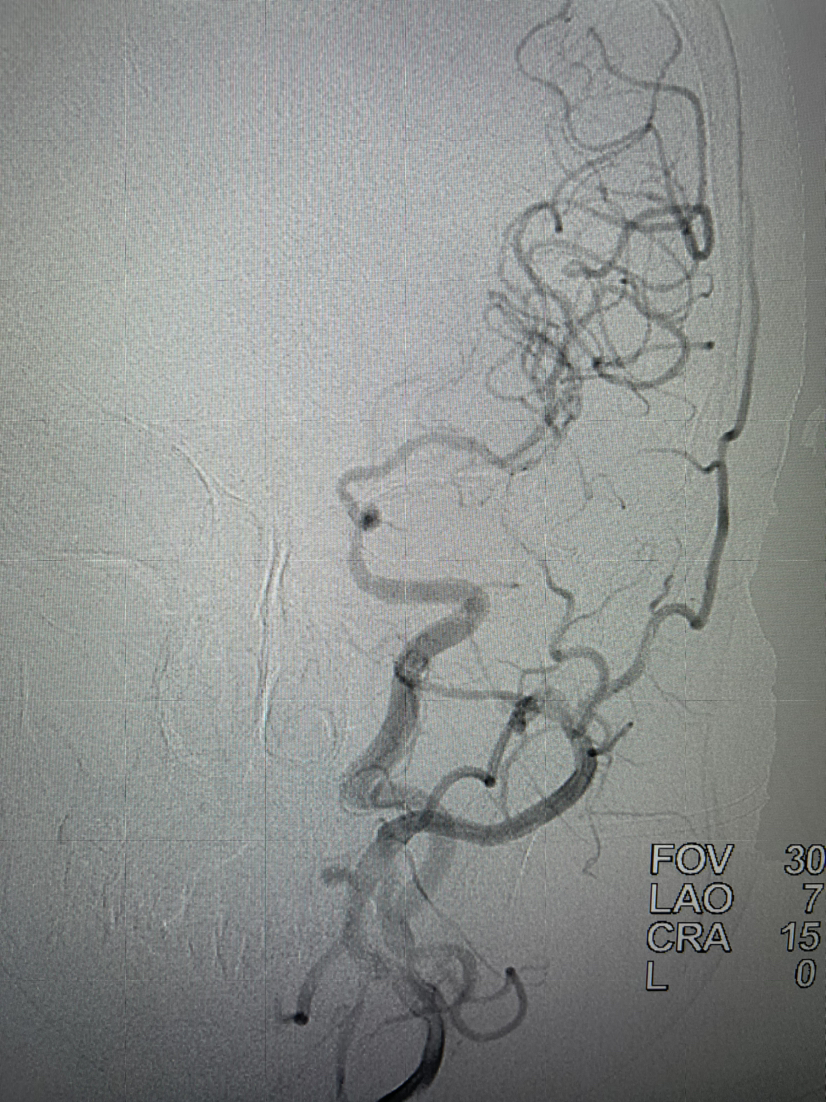

球囊扩张后颈内动脉起始部狭窄明显好转

颈动脉支架植入

支架植入后正位

支架植入后侧位